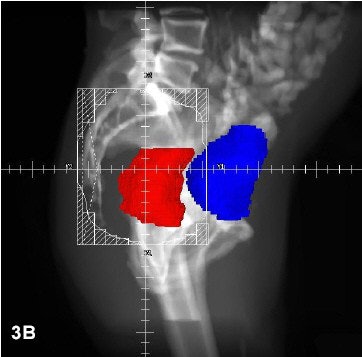

Three radiation fields (PA with right and left lateral) were used for all patients, using CT-based 3-D treatment planning. Rectum is red; bladder is blue.